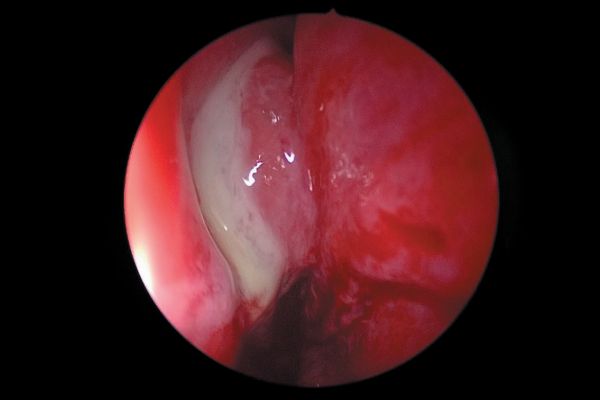

Sialoendoscopia en las patologías obstructivas de las glándulas salivales

RETIRADA DE IMPLANTE ENDOSINUSAL MEDIANTE ABORDAJE ENDOSCÓPICO. A PROPÓSITO DE UN CASO